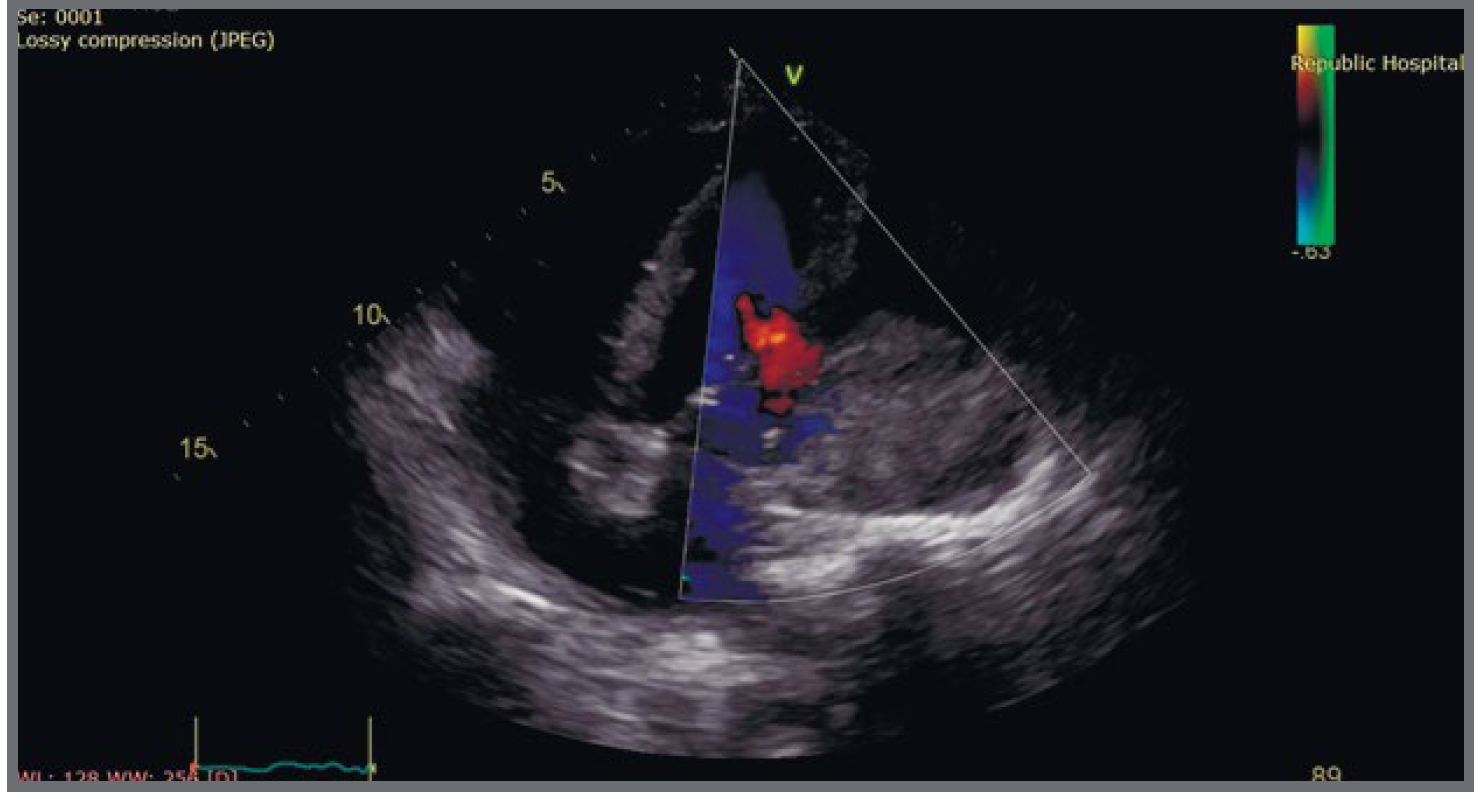

Пациентка 65 лет госпитализирована в ревматологическое отделение ГБУЗ «Республиканская больница им. В.А. Баранова» 12 марта 2019 г. Ревматоидный артрит (РА) диагностирован в 2014 г., сопутствующая патология – гипертоническая болезнь и СД типа 2 – СД 2 (терапия метформином, гликлазидом). При назначении сульфасалазина, метотрексата – лейкопения до 3,4–2,9 г/л, с отменой препаратов, эпизодический прием нестероидных противовоспалительных средств. В августе 2018 г. в связи лихорадкой, панцитопенией обследована в ревматологическом отделении, диагностирован перекрестный синдром: системная красная волчанка (СКВ) и РА. При назначении ГК – стойкая нормализация температуры, гематологических показателей. С 03.12.2018 – вновь лихорадка, госпитализирована в центральную районную больницу по месту жительства, диагностирован острый бронхит, получала цефотаксим (длительность и дозы неизвестны) с некоторой положительной клинико-лабораторной динамикой. После выписки – боли в области правой ягодицы, лихорадка. С 30.01.2019 по 12.02.2019 – лечение в хирургическом отделении больницы скорой медицинской помощи по поводу абсцесса ягодичной области: дренирование абсцесса, антимикробная терапия. После выписки – эпизод давящих болей за грудиной, обращалась в приемный покой центральной районной больницы, с 20.02.2019 по 12.03.2019 – лечение в терапевтическом отделении по поводу внебольничной левосторонней нижнедолевой пневмонии. Антимикробная терапия меропенемом, затем левофлоксацином. В анализах: скорость оседания эритроцитов 60–43 мм/ч, С-реактивный белок 88–155–93 мг/л. При эхокардиоскопии (ЭхоКС) от 21.02.2019: объемное образование средостения, левого легкого? Переведена в ревматологическое отделение ГБУЗ «Республиканская больница им. В.А. Баранова» для уточнения характера поражения легких. При поступлении: жалобы на боли в подреберьях, спине, из-за боли не может передвигаться, спать. Одышка при минимальной физической нагрузке, не лихорадит, масса тела стабильна. Выполняется спиральная компьютерная томография (СКТ) грудной полости (12.03.2019), где визуализируется компьютерно-томографическая (КТ) картина спондилита, спондилодисцита на уровне ThVII, ThVIII с выраженным паравертебральным мягкотканым компонентом, при этом рекомендуется ультразвуковое исследование сердца ввиду неясного характера изменений в левом гемитораксе (рис. 1).

Рис. 1. КТ позвоночника спиральная.

Fig. 1. Spiral CT of the spine.